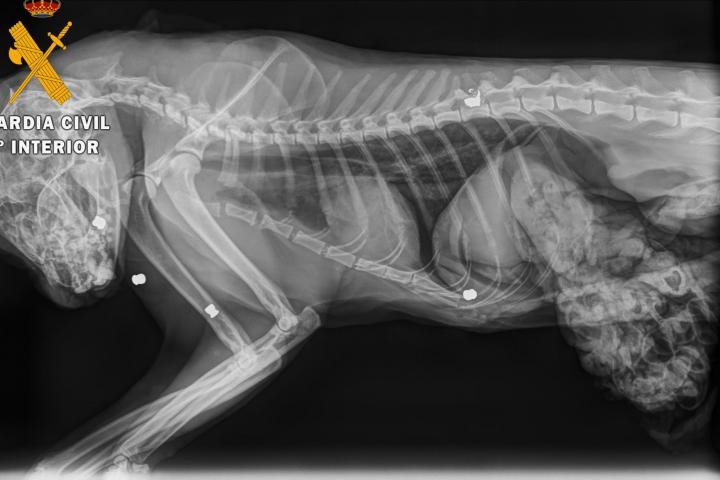

Al cuerpo del gato se le realizó una necropsia en una clínica veterinaria de Estella, donde se determinó que el animal había fallecido por el impacto de cinco perdigones. Se extrajo uno de los cinco proyectiles por si fuese necesario para un análisis.